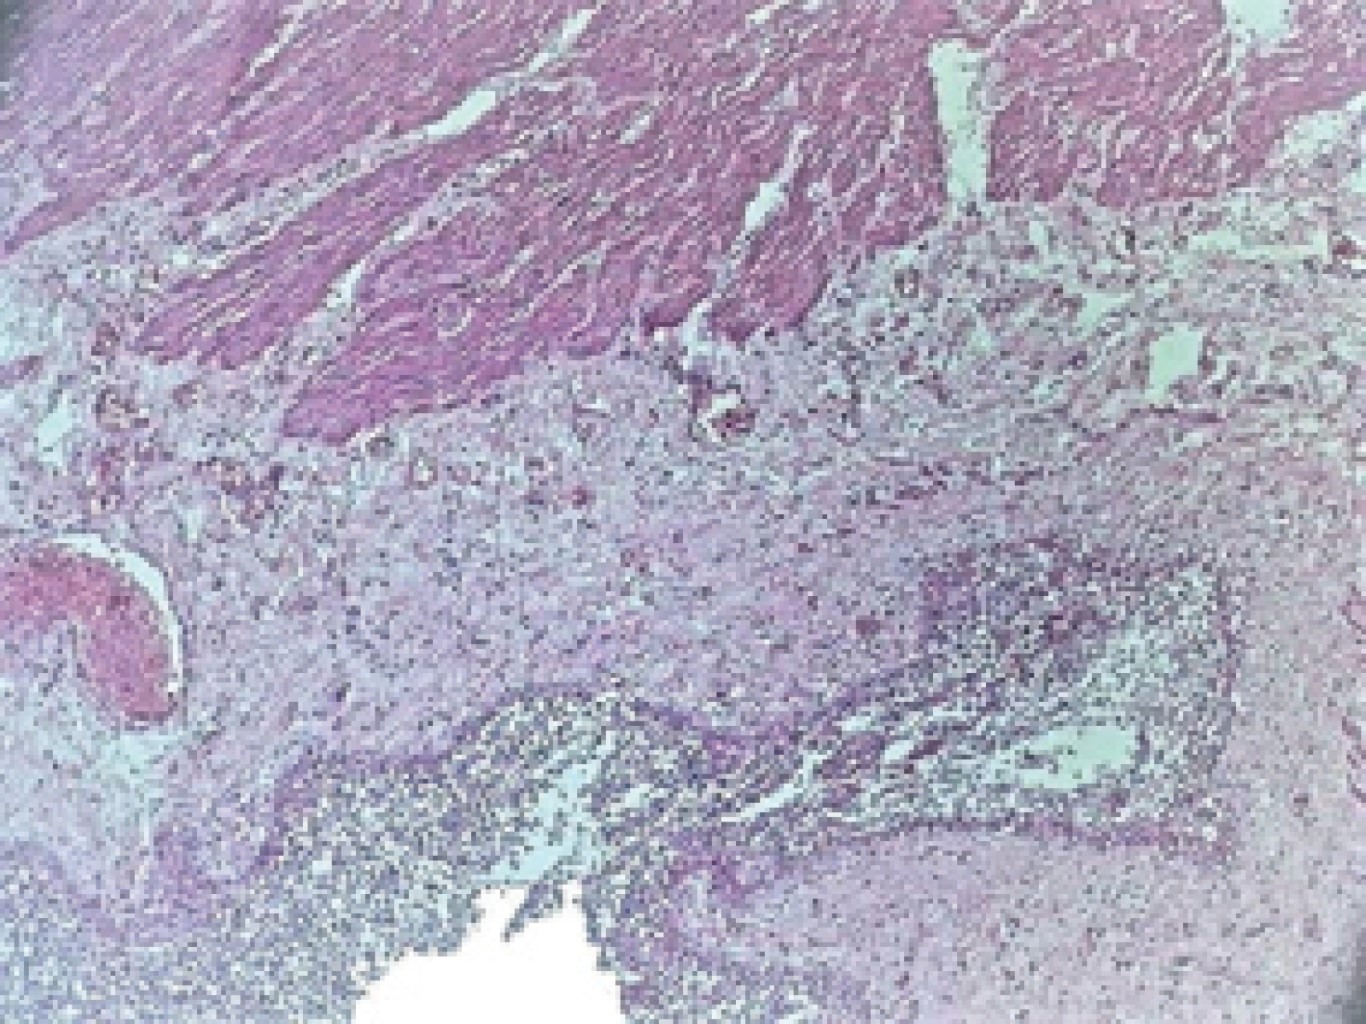

The histopathological report corroborated the clinical diagnosis, showing a thin wall with congestion and perforated diverticular disease leading to acute peritonitis (Figures 3, 4, 5, 6 and 7).

Figure 7